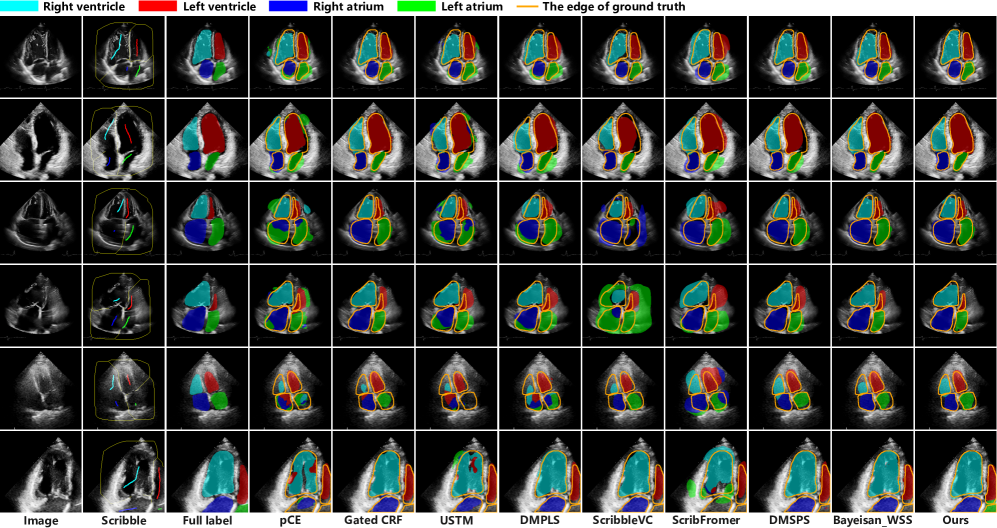

Refer to caption

Figure 5: Visualization of experimental results comparison on the CardiacUDA dataset. The Scribble column represents scribble annotations, while the Full label column indicates full dense annotations. The yellow lines indicate the ground truth.

The quantitative results of all methods obtained from the experiments on the challenging CardiacUDA dataset are presented in Table 1. As can be seen from the table, The baseline method, pCE, performed mediocrely and served as a benchmark for scribble-supervised segmentation performance. The performance of all other methods surpassed that of pCE. Among the existing methods, Gated CRF exhibited commendable performance, ranking second only to the proposed approach, with the mean Dice score of 74.62% and the 95HD of 11.74. This suggested that Gated CRF holds an advantage in the task of scribble-supervised segmentation on ultrasound datasets, attributed to its capability of perceiving morphological features of anatomical structures. Our proposed method achieved the highest performance on all evaluation metrics for the scribble-supervised task on this dataset, with the mean Dice score of 75.39% and the 95HD of 11.60, outperforming Gated CRF by 0.77% in Dice score. This may stem from the model’s tendency to prioritize learning easily segmentable classes, thereby introducing unfairness. In contrast, our method not only achieved overall superior segmentation performance but also demonstrated a narrower performance gap among different classes, highlighting its superiority and robustness.

We visualized the segmentation results as shown in Figure 5, aiming to provide a clear and intuitive understanding of the performance differences between various methods. As seen from the figure, the images in the first and second rows exhibited higher quality and clearer boundaries compared to other rows, resulting in overall better segmentation outcomes. Most segmentation methods committed errors in segmenting the images in the third and fourth rows, whereas our method avoided the severe mistake of misidentifying anatomical structural locations. The sixth row shows that other methods failed to segment the left atrium, whereas our approach successfully achieved it. In relative terms, pCE, USTM, and DMPLS exhibited a higher number of segmentation error regions. From the figure, we observed that the most prevalent error was the misidentification of other cardiac chambers as the left atrium, likely attributed to the small proportion of the left atrium’s area in most echocardiographic images, rendering it challenging for weakly supervised models to adequately capture the characteristics of the left atrium. Furthermore, our observations revealed that ScribbleVC tended to adopt a conservative approach in segmenting certain regions, such as the left and right ventricles in the figure, failing to fully delineate the target objects. Conversely, it exhibited a more aggressive segmentation in other regions, like the left and right atria in the figure, by erroneously including substantial non-target areas within the segmentation. While it has been reported to excel in magnetic resonance image segmentation in the literature [39], it may not be adaptable to the segmentation of ultrasound images.